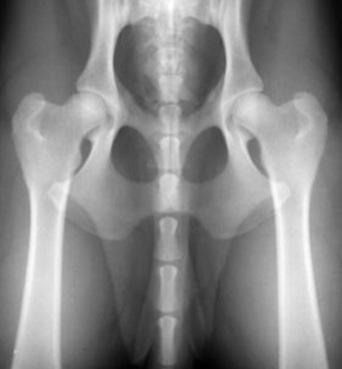

Jäsenhinnat luustokuvauksille:

– Lonkat ja kyynärät alle 40kg koira 152 €

– Lonkat ja kyynärät yli 40g koira 173 €

– Lonkkakuvaus ilman kyynäriä 150 €Ylläoleviin lisäksi, jos kuvataan: